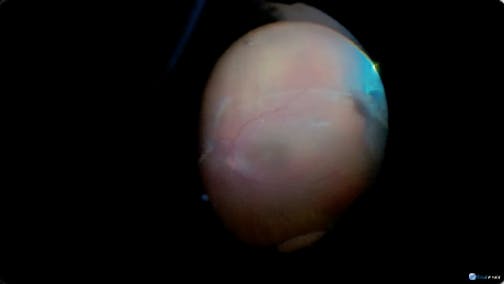

Retinal Detachment

Kazuaki Kadonosono, MD